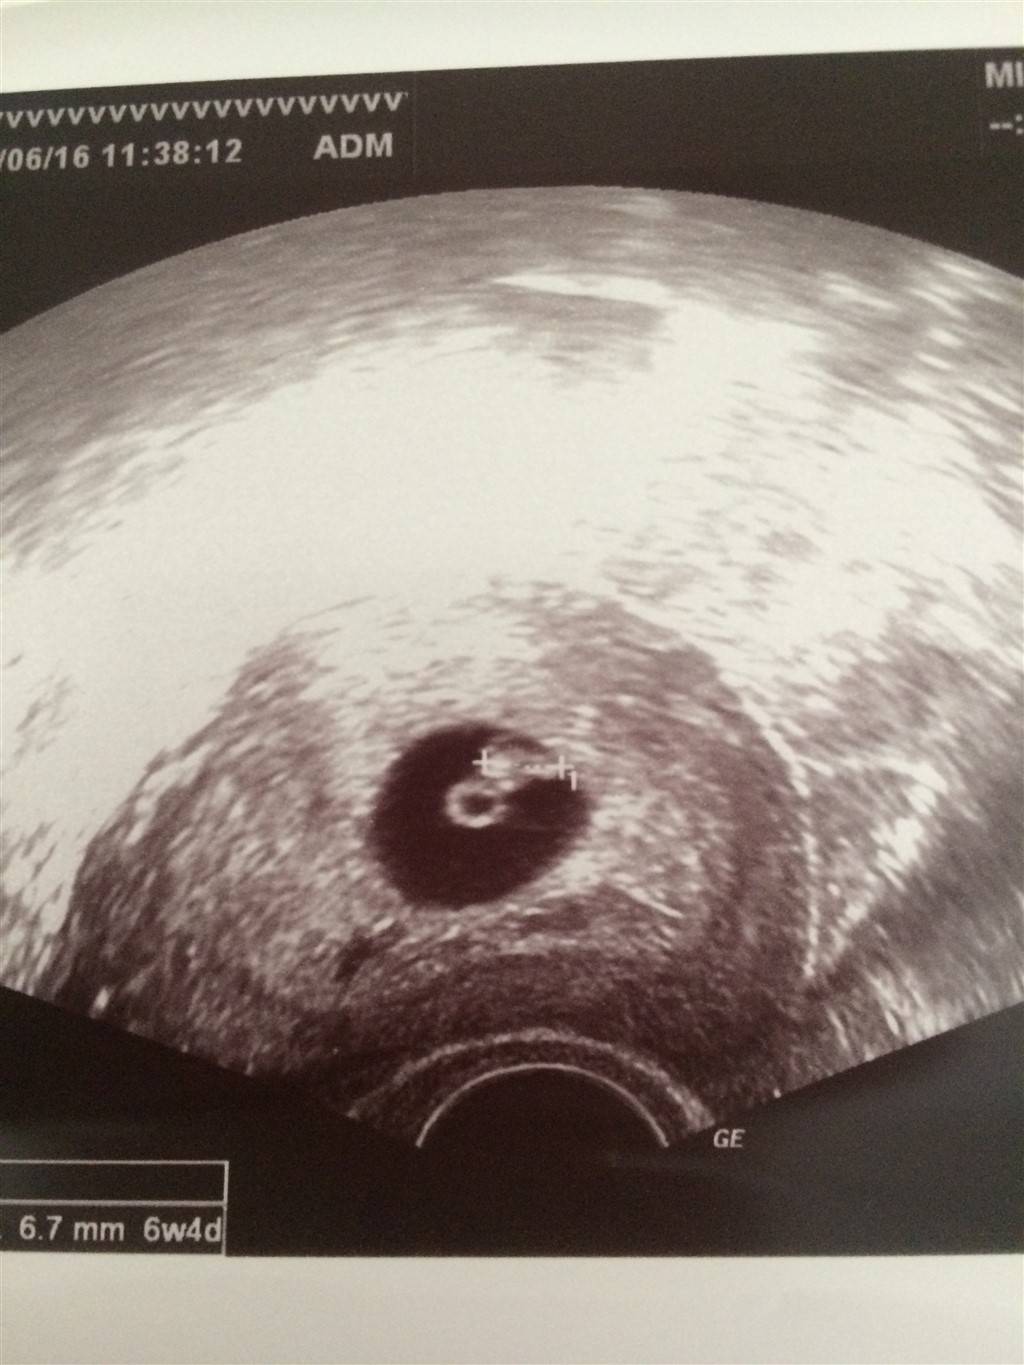

Tillykke med spirren